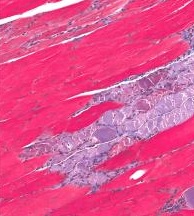

La myostatine est une protéine naturellement produite dans le corps qui inhibe la croissance musculaire, rappelle le Dr Stuart Warden, professeur agrégé et auteur principal de l'étude. Le rôle de la myostatine est en effet de contrôler la réparation et la croissance musculaire en bloquant la prolifération des cellules musculaires. Plusieurs études y ont donc déjà vu une cible prometteuse pour le traitement de certaines myodystrophies (Voir visuel "muscle avec dystrophie" ci-contre). En effet, inhiber l'activité de cette molécule peut permettre de prolonger la prolifération des cellules musculaires, augmenter la masse et la puissance musculaires. Certains sportifs y ont également vu des bénéfices musculaires… Finalement, cette étude apporte à la preuve que l'inhibition de la myostatine peut permettre aux muscles de se développer ou a minima de ne pas décliner.